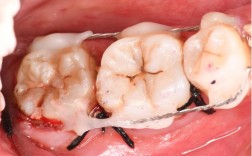

种植体植入手术(1-2小时)

在局部麻醉下,切开牙龈、暴露牙槽骨,使用专用钻逐级备洞后将种植体(纯钛材质,生物相容性极佳)植入牙槽骨内,年轻人因骨条件好,部分可实现“即刻种植”(即拔牙后立即植入种植体),缩短缺牙等待期;若需植骨,则分两阶段进行。